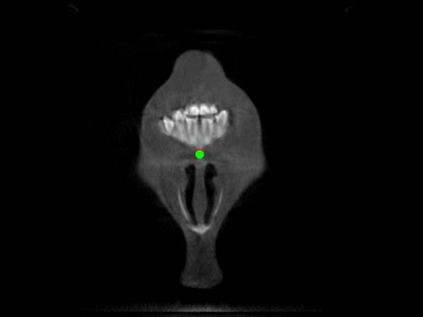

Detecting 3D landmarks on cone-beam computed tomography (CBCT) is crucial to assessing and quantifying the anatomical abnormalities in 3D cephalometric analysis. However, the current methods are time-consuming and suffer from large biases in landmark localization, leading to unreliable diagnosis results. In this work, we propose a novel Structure-Aware Long Short-Term Memory framework (SA-LSTM) for efficient and accurate 3D landmark detection. To reduce the computational burden, SA-LSTM is designed in two stages. It first locates the coarse landmarks via heatmap regression on a down-sampled CBCT volume and then progressively refines landmarks by attentive offset regression using multi-resolution cropped patches. To boost accuracy, SA-LSTM captures global-local dependence among the cropping patches via self-attention. Specifically, a novel graph attention module implicitly encodes the landmark's global structure to rationalize the predicted position. Moreover, a novel attention-gated module recursively filters irrelevant local features and maintains high-confident local predictions for aggregating the final result. Experiments conducted on an in-house dataset and a public dataset show that our method outperforms state-of-the-art methods, achieving 1.64 mm and 2.37 mm average errors, respectively. Furthermore, our method is very efficient, taking only 0.5 seconds for inferring the whole CBCT volume of resolution 768$\times$768$\times$576.